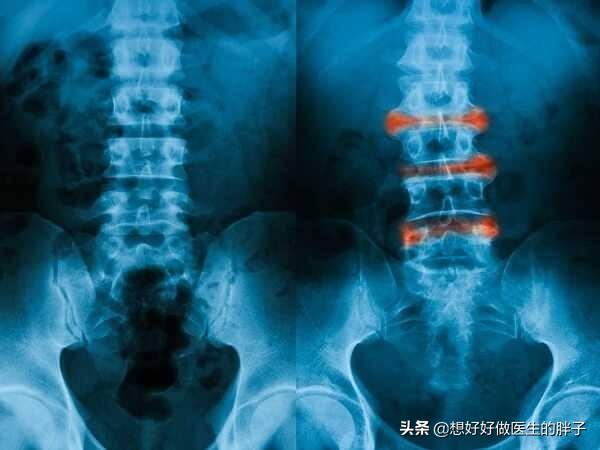

强直性脊柱炎属于风湿免疫科的疾病。具体的原因到现在也不是非常的明确。这种疾病主要累及骶髂关节、脊柱以及一些大的关节。病变的部位会发生比较严重的纤维化、骨化。患者出现疼痛以及日渐加重的活动受限。

强直性脊柱炎中晚期脊柱活动受限。检查x线可以发现典型的竹节样改变。诊断往往不难。早期诊断却容易和腰疼混淆。导致遗漏。早期的强直性脊柱炎患者以下的一些特点:

强直性脊柱炎是一种严重危害人类健康的风湿免疫性疾病。是一种是以骶髂关节和脊柱附着点炎症为主要症状的疾病。主要影响脊柱、胸腔和骨盆的关节。这几处的关节会生长粘连在一起。时间长了。脊柱就会失去灵活性。

强直性脊柱炎的可怕之处不仅仅是发作起来疼的要死。严重影响生活质量。更可怕的是病情控制不佳的话。晚期可发生脊柱畸形和关节强直。致残和致死风险增高的同时。